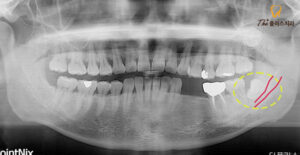

위 환자분은 하악

좌측 소구치 임플란트 식립을 위해

본 원에 내원해 주셨는데요.

식립 전 정밀한 진단을 위해

파노라마 사진을 먼저 찍어보았습니다.

임플란트 식립을 위해 내원해 주셨지만

맨 안쪽에 위치하는 사랑니도

큰 문제가 있었는데요.

사진 판독 결과 사랑니로 인해

대구치 뒷쪽 치조골이

소실 되어 있는 상태였습니다.

환자분께서도 하악 좌측 맨 안쪽 어금니에

한 번씩 통증이 있고

시린 느낌이 있었다고 하셨습니다.

치조골의 상당 부분이

소실된 상태라 예후가 좋지 않아

사랑니와 함께 앞에 위치한

대구치도 발치를 진행하기로 하셨습니다.

사랑니를 발치해야 할 때는 맹출 방향과,

뿌리가 휘어진 정도,

신경관과의 거리 등을

면밀히 살펴보는 것이 중요한데요.

특히 환자분의 경우에는

사랑니가 하치조신경관과

중첩되어 있는 것으로 보여

위치를 세심하게 파악하기 위해

3D CT 촬영을 진행하였습니다.